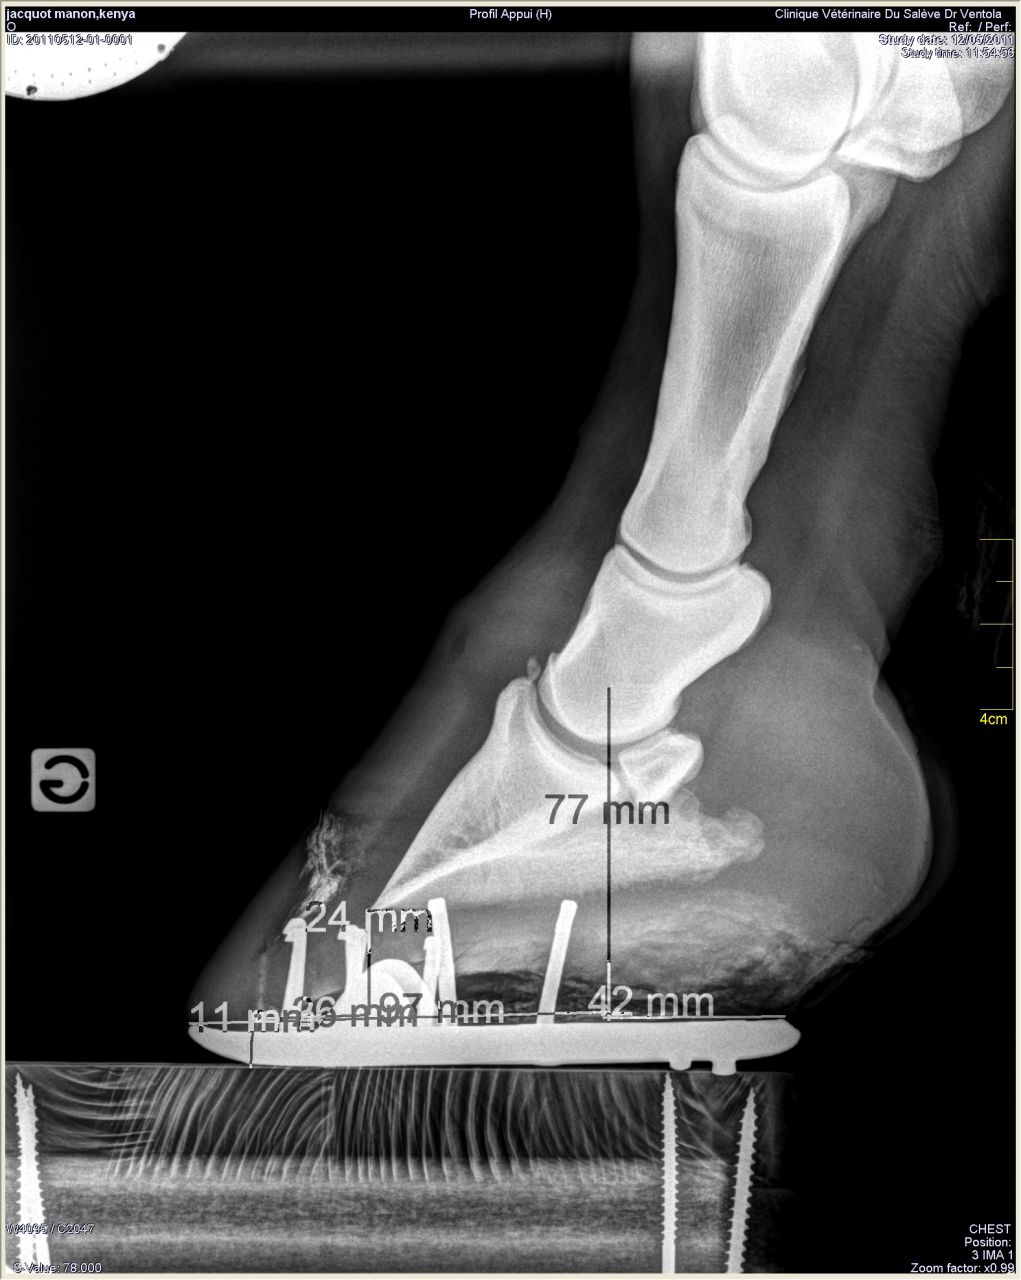

| Dire merci | Donc les radios: Antérieur gauche de profil où on peut voir le petit bout d'os au somment entre les phalanges 2 et 3 ![]() On peut noter un autre souci: normalement le milieu de la 2ème phalange doit être aligner avec le milieu du pied (c'est ce que représente le trait vertical marqué 77mm). Or ici le pied est à 2/3 devant. Ce qui a un effet levier et fatigue donc les tendons de la jument. Le pied gauche de face à plat: ![]() On peut remarquer que la 1ère phalange n'est pas nette (le véto m'a dit qu'on dirait une radio d'un cheval de 20ans.... :/) Le pied gauche de face en extension: ![]() |